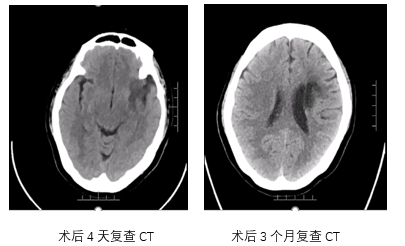

• 术后一天:DWI显示梗塞面积没有明显增大,MRA提示血管再通,发现存在LMCA动脉瘤。

病历夹什么径技·第151期|串联营病历夹:京广连营_https://www.jmylbn.com_新闻资讯_第72张

病历夹什么径技·第151期|串联营病历夹:京广连营_https://www.jmylbn.com_新闻资讯_第73张

病历夹什么径技·第151期|串联营病历夹:京广连营_https://www.jmylbn.com_新闻资讯_第74张

结论:颅脑CT提示左侧基底节、放射冠区腔隙样软化灶。颅脑DWI提示双侧小脑、桥脑、中脑、双侧海马、双侧枕叶、右侧丘脑及右侧胼胝体多发急性脑梗塞。颅脑MRA提示基底动脉及双侧大脑后动脉未见显示;右侧大脑中动脉中-重度狭窄;脑动脉硬化。初步诊断为急性后循环脑梗死,基底动脉闭塞。